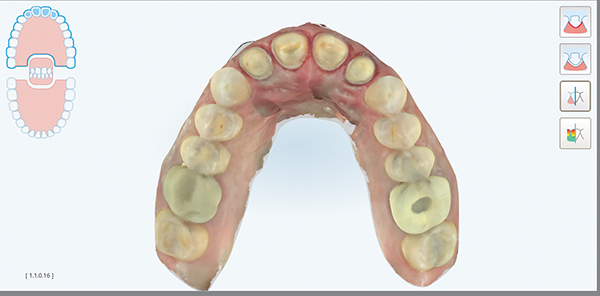

Fig 2. Occlusal view highlighting the erosive wear present on the lingual aspects of the maxillary anterior teeth with a preserved enamel ring around the gingival margin.

Figure 2